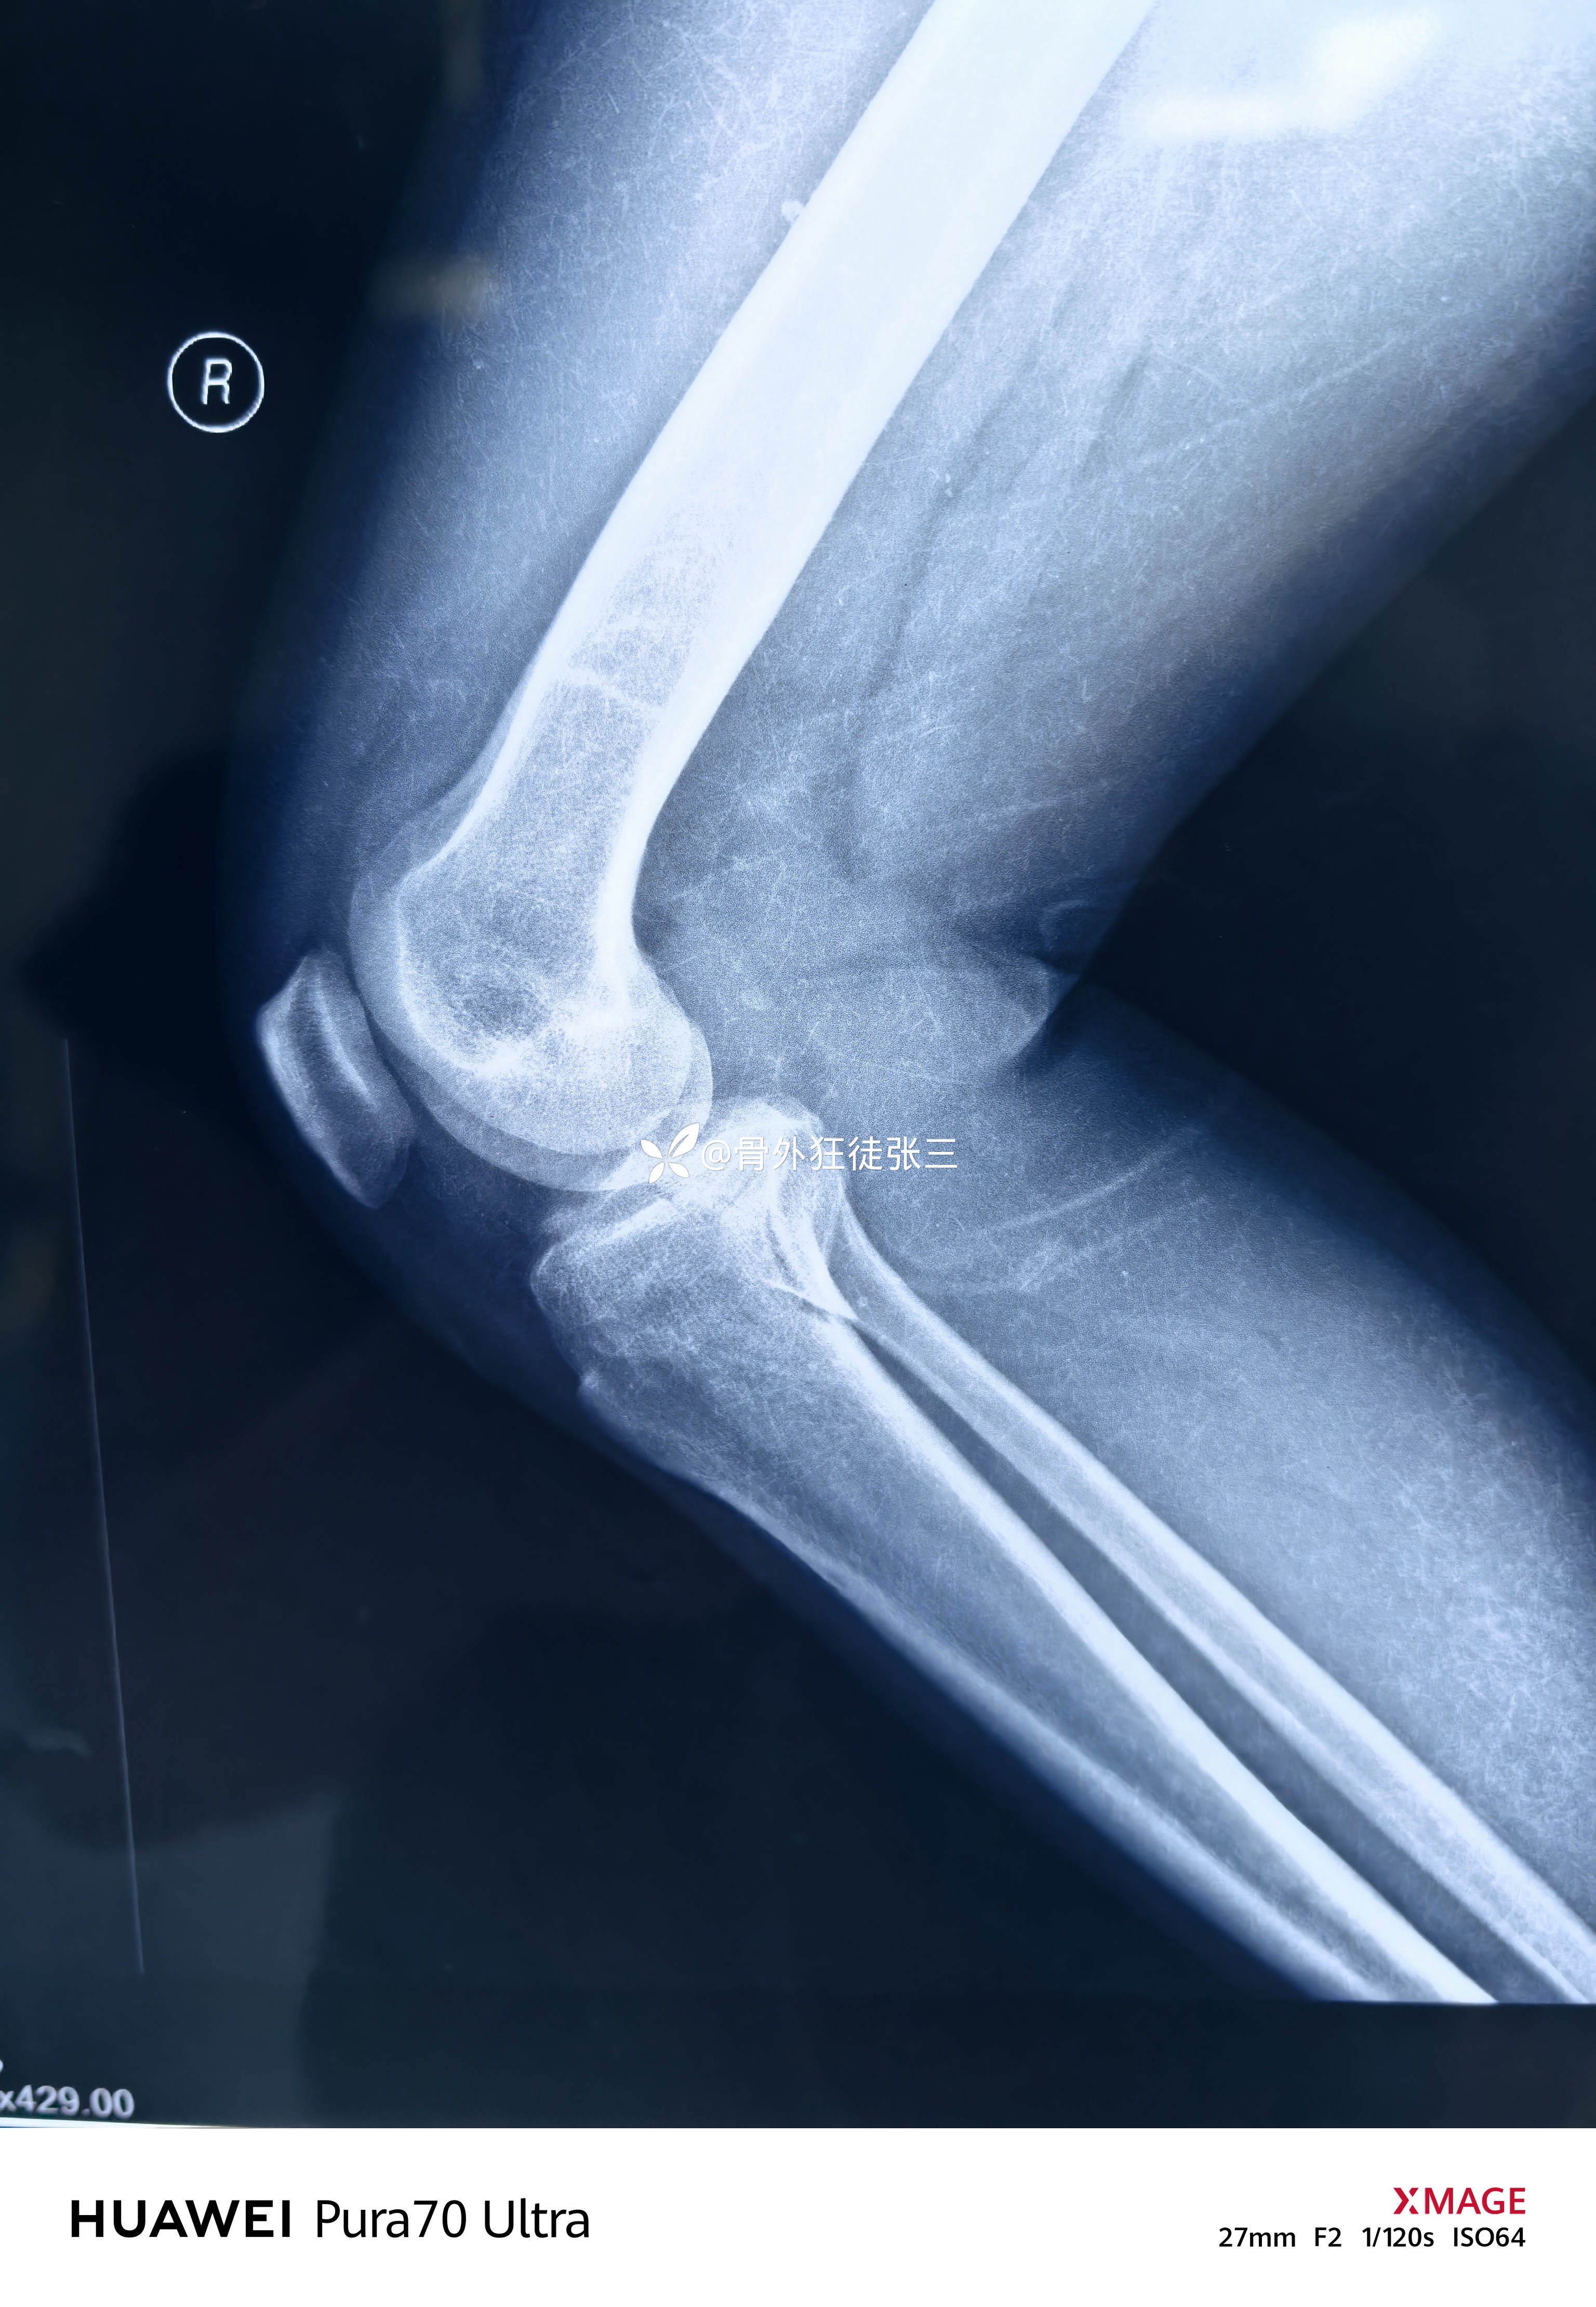

虽然X线平平无奇

右胫骨平台骨折

(屈曲内翻型——后内侧平台骨折+外侧平台塌陷+ACL止点撕脱)